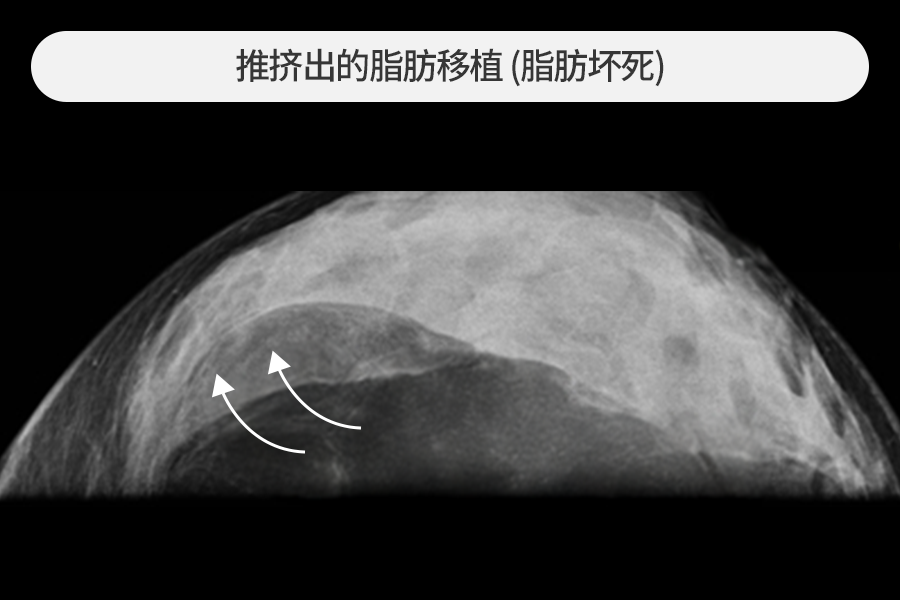

4~5cm 大小的脂肪移植硬块去除

该患者因胸部脂肪移植后摸到乳房硬块而来院,观察到4~5cm大小的巨大钙化硬块。

尺寸较大的脂肪移植硬块发生急性炎症时风险较高,需要尽快去除。

在超声引导下保留正常组织,仅安全去除了硬块。